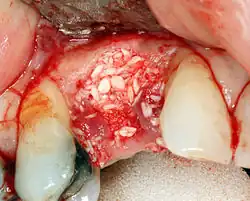

Реконструкция твёрдых тканей

Разборный имплантат

Разборный имплантат состоит из непосредственно имплантата и надстройки (супраструктуры), именуемой абатментом. Такой имплантат может быть установлен по одно- и двухэтапному протоколу. Двухэтапный протокол подразумевает полное погружение имплантата и накрывание его слизистой оболочкой, в результате чего исключается любой контакт имплантата с полостью рта — эта процедура называется первым этапом дентальной имплантации. Второй этап заключается в установке какой-либо надстройки (супраструктуры) — это может быть как формирователь десны, так и абатмент с временной коронкой или другим видом протезной конструкции. После какого промежутка времени будет выполнен второй этап обычно решает имплантолог, опираясь на данные о качестве костной ткани, возраст и общее состояние пациента, а также свой клинический опыт. Классические сроки составляют 4—6 месяцев, однако последнее время существует тенденция к сокращению сроков ожидания до 2,5—3 месяцев. Это связано с лучшим пониманием процесса остеоинтеграции, а также оптимизацией макродизайна и микрохарактеристик поверхности имплантатов.